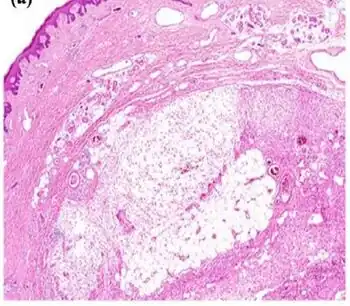

As examined by gross pathology, AMSF tumors are typically lobulated, with gelatinous, fleshy, or firm areas that vary in color and texture; they are most often localized to subcutaneous adipose tissue but may infiltrate into nearby tissues.[4] Histopathologic microscopic examinations of hematoxylin and eosin stained tumors characteristically show spindle-shaped cells admixed with prominent inflammation-like areas containing a mixture of neutrophils, lymphocytes, and plasma cells. The areas of these lesions that contain spindle cells are often also occupied by distinctively large, variably-shaped epithelioid cells that have vesicle-laden nuclei and acidophilic (readily stained with acid dyes) nucleoli. These cells have been termed Reed-Sternberg cell-like, virocyte-like (i.e. cells which, similar to some viruses, have sticklike protrusions), and ganglion cell-like. The tumors may also contain large vacuolated pseudolipoblasts (i.e. cells that resemble lipoblasts). These various cell types are embedded in a myxoid (i.e. more blue or purple compared to normal connective tissue because of excessive uptake of the hematoxylin stain) and collagen fiber-laden tissue background.[5] In addition to the cited cell types, the tumors may contain degenerated, dying, and or dead cells and large histiocyte-like cells that have engulfed other cells, usually neutrophils (this cell-engulfing phenomenon is termed emperipolesis).[4] In one large study, emperipolesis of white blood cells appeared to be a helpful indicator of AMSF.[10]) The proportions, numbers, and types of these cells varies greatly among cases and thereby may present diagnostic challenges. For example, AMSF tumors can have dense inflammatory infiltrates which obscure other cell types and thereby suggest that the lesion is a purely inflammatory reaction.[5]